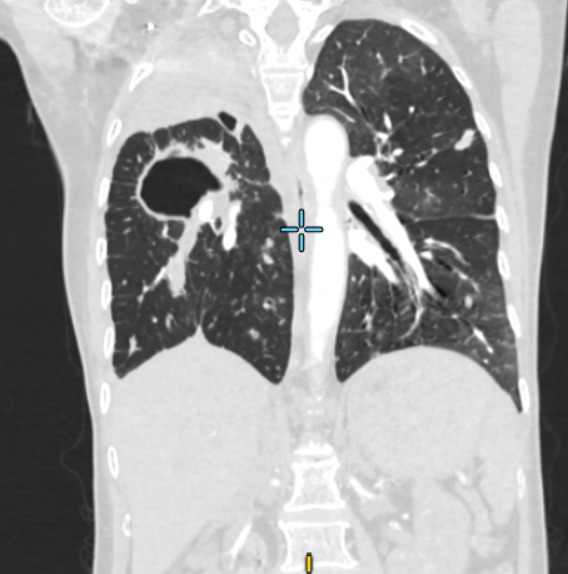

Ngay khi tiếp nhận tại khoa Cấp Cứu, các bác sĩ đã nhanh chóng đặt ống nội khí quản để thở máy nhằm duy trì sự sống cho người bệnh. Đồng thời, các bác sĩ khẩn trương chụp CT ngực có tiêm thuốc cản quang thì phát hiện tổn thương lan tỏa ở cả hai phổi – nghi ngờ lao phổi, khí phế quản hai bên đọng nhiều máu. Kết quả xét nghiệm sau đó xác nhận bệnh nhân dương tính với lao phổi.

Hình ảnh CT tổn thương phổi do ho ra máu